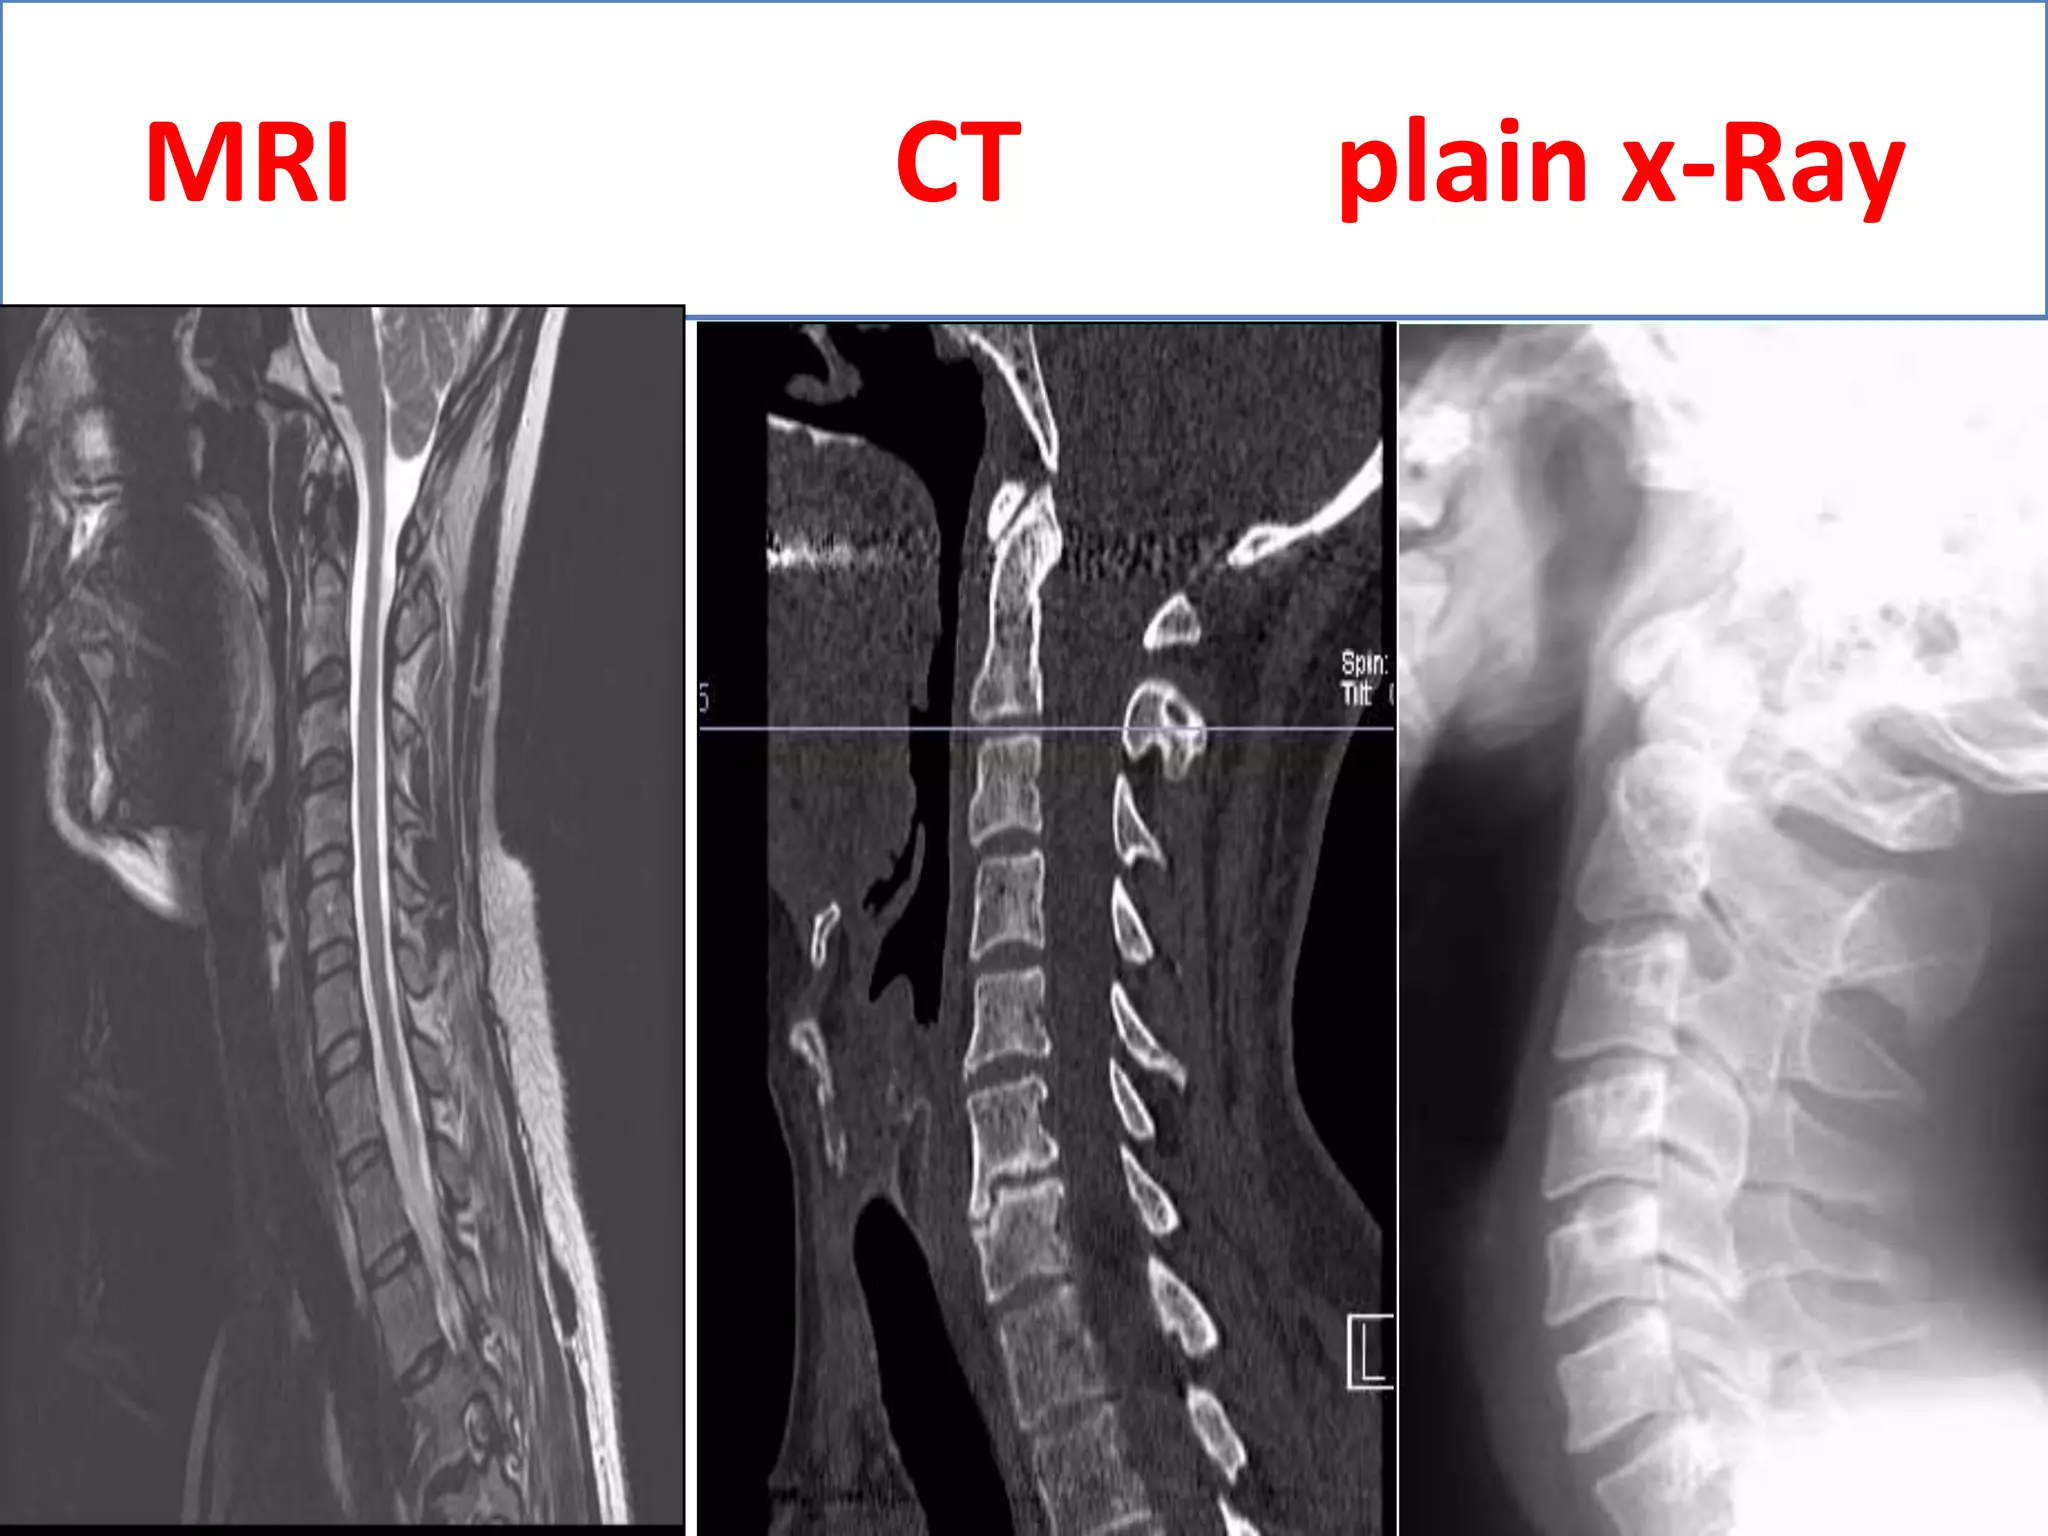

MRI                   CT           plain x-Ray